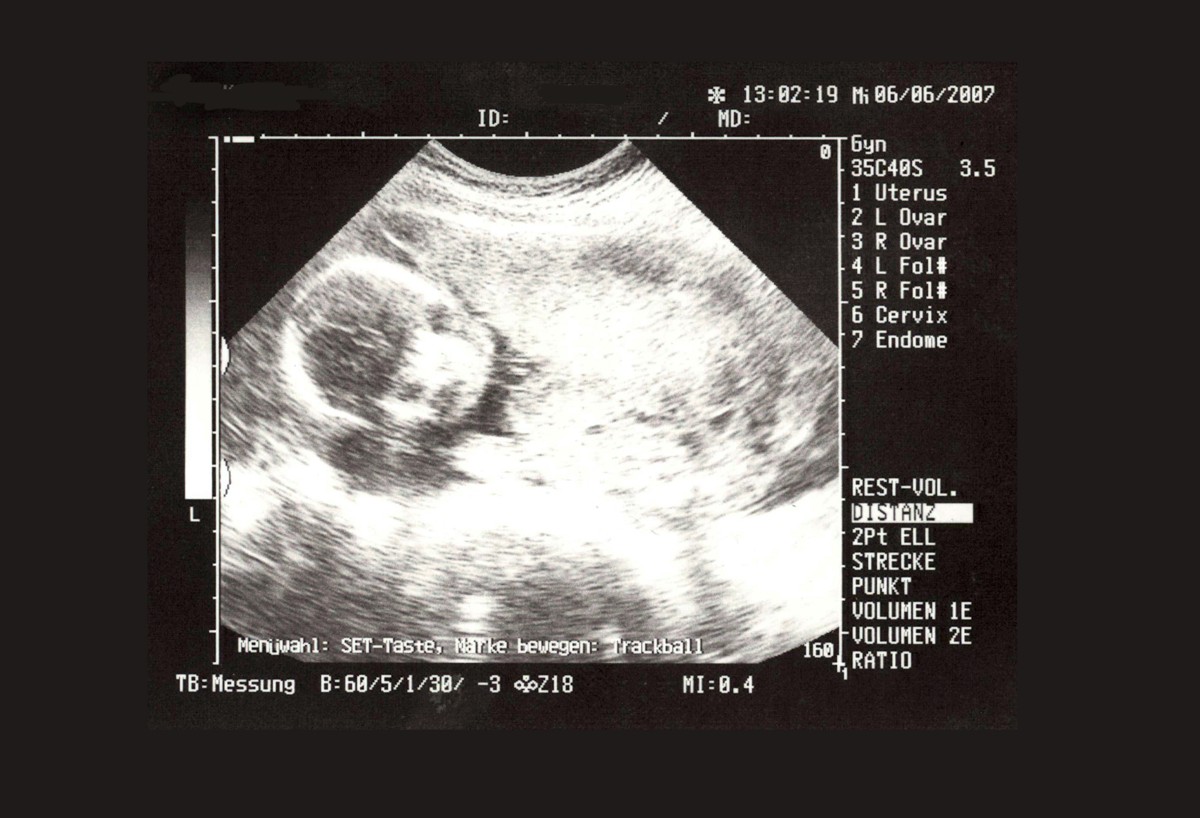

- diagnostika gravidity, prenatálná starostlivosť

- pravidelné tehotenské prehliadky

- ultrazvuk

Ultrazvuk